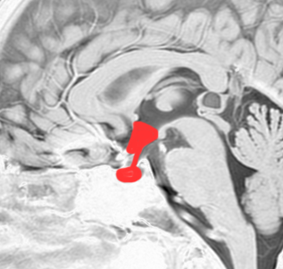

- 下垂体とは脳のほぼ真ん中の底部で視床下部と視交叉(両側の視神経が交叉するところ)の下にある小指の先くらいの小さい組織です

頭蓋骨を透して下垂体腺腫を見たものです。両目の間,頭の中心に緑色に塗ったのが下垂体腺腫です。頭蓋底の鼻腔の奥にあるともいえます。赤い色は動脈,青い色は静脈で,多くの血管に囲まれています。

下垂体へ到達するには,黒い矢印のように鼻の孔からのぞいて鼻腔を通って,空色に塗った蝶形骨洞というところを通っていくので,これを経蝶形骨洞手術 transsphenoidal surgery TSSと言います。下垂体腺腫にもっともよく用いられる手術法です。気をつけなければならないのは,海綿状脈洞に伸びている腫瘍を手術で摘出しようと言われたときです。海綿静脈洞内部の手術は開頭手術になることもあり危険性は高いといえます。時には死亡例もあるので手術の内容はしっかり聞いて下さい。